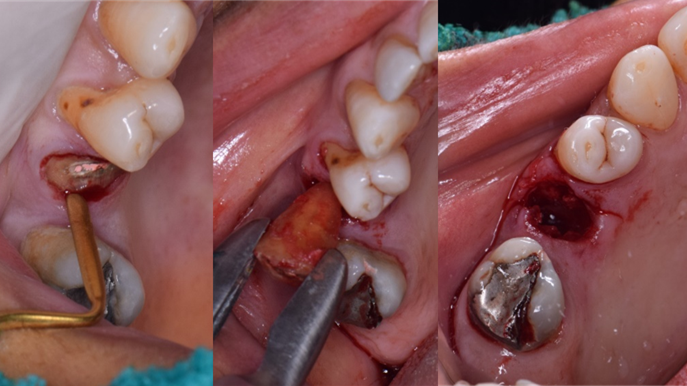

Clinical case: R2GATE GUIDE surgery with GBR

- Courtesy of Dr. Kwang Bum Park, Korea -

Dr. Kwang Bum Park, digital guided surgery, bone regeneration, maxillary posterior, #13, #14, guided surgery, GBR, AnyRidge, i-GEN, Mega-Oss, R2GATE, R2GATE Full surgical kit